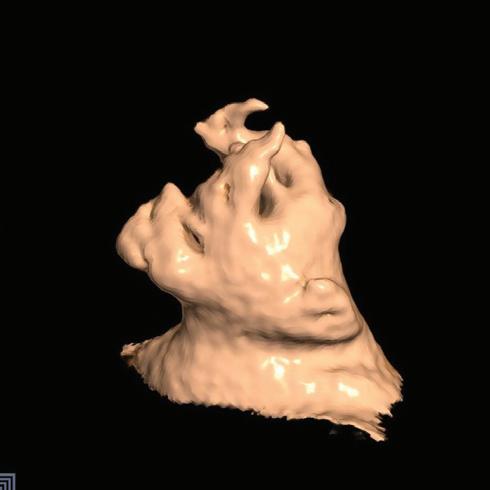

Figure 6: Ventricular Ablation Lesion Assessment

Preprocedural LGE-MRI (1 day before VT ablation)

Ablation points

Post-ablation LGE-MRI (3 months after VT ablation)

Left: 3D reconstruction of the left ventricle with LGE-based colour-coding based on thresholds for dense scar (red, >60% maximum of signal intensity) and border zone (yellow, 40–60% of maximum signal intensity), mapped using ADAS 3D. Shown are the layers at 30% of the transmurality (from endocardial to epicardial). For the post-ablation LGE-MRI (lower panel), an additional 3D reconstruction of the manually defined dark core in red (black arrow) is depicted. Blue lines indicate the plane of the short-axis slices on the right. The ablation points (TactiCath, Abbott Medical) are visualised using a 3D mapping system (EnSite Precision, Abbott Medical). Middle: Overlay of the T1-weighted short-axis slices with the colour-coding described above. The central hypoenhancement dark core of the ablation lesion is manually delineated (red border) to avoid misinterpretation as healthy tissue. Right: T1-weighted short-axis LGE-MRI slices without colour-coding. LGE = late gadolinium enhancement; VT = ventricular tachycardia.